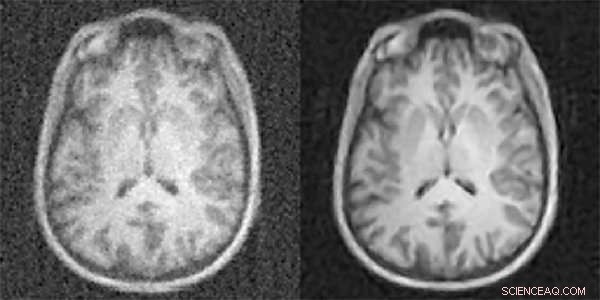

A new artificial-intelligence-based approach to image reconstruction -- called AUTOMAP -- yields higher quality images from less data, reducing radiation doses for CT and PET and shortening scan times for MRI. Shown here are MR images reconstructed from the same data with conventional approaches (left) and AUTOMAP (right). Credit: Athinoula A. Martinos Center for Biomedical Imaging, Massachusetts General Hospital

A radiologist's ability to make accurate diagnoses from high-quality diagnostic imaging studies directly impacts patient outcome. However, acquiring sufficient data to generate the best quality imaging comes at a cost - increased radiation dose for computed tomography (CT) and positron emission tomography (PET) or uncomfortably long scan times for magnetic resonance imaging (MRI). Now researchers with the Athinoula A. Martinos Center for Biomedical Imaging at Massachusetts General Hospital (MGH) have addressed this challenge with a new technique based on artificial intelligence and machine learning, enabling clinicians to acquire higher quality images without having to collect additional data. They describe the technique - dubbed AUTOMAP (automated transform by manifold approximation) - in a paper published today in the journal Nature.